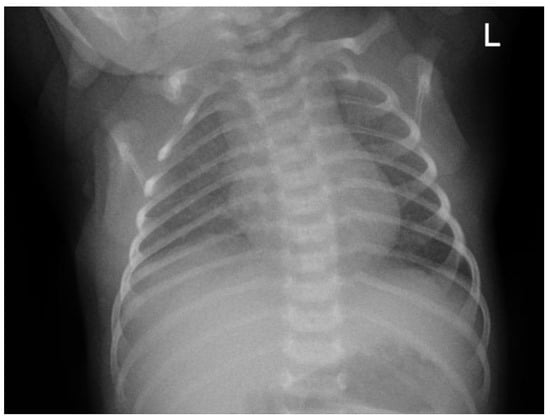

Upon initial examination, the patient exhibited respiratory distress, with grunting, subcostal chest retractions, and an SpO2 of 81% on room air. Oxygen supplementation was initiated using continuous positive airway pressure (CPAP), resulting in an improved oxygen saturation of 98%. A chest X-ray was performed, revealing pneumonia (Figure 5a). However, during monitoring, the patient’s respiratory distress worsened, with a decline in oxygen saturation and episodes of periodic apnea, necessitating intubation. The patient was subsequently transferred to the NICU for further respiratory support. Initial and follow-up blood laboratory findings are summarized in Table 2.

By day 9 in the NICU, the patient’s general condition had stabilized, and extubation was performed (Figure 5b). On day 10 of hospitalization, the patient was transferred to the neonatal high-care unit (NHCU) for continued monitoring and supportive care. The patient remained in the NHCU for an additional 5 days, during which antibiotic therapy was continued, with cefotaxime given for a total of 12 days.

Figure 5. Anteroposterior (AP) chest X-ray showing (a) bilateral pneumonia on admission to the emergency department (ED) and (b) improvement in pneumonia on day 9 of hospitalization before extubation. “L”: an anatomical marker indicating the left side.